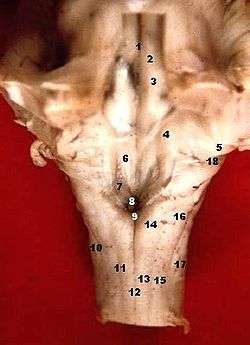

Human caudal brainstem posterior view (The sulcus limitans separates #2 from #4.) | |

In the floor of the fourth ventricle, the sulcus limitans separates the cranial nerve motor nuclei (medial) from the sensory nuclei (lateral).[1] In the superior part of the rhomboid fossa, it corresponds with the lateral limit of the fossa and presents a bluish-gray area, the locus ceruleus (which owes its color to an underlying patch of deeply pigmented nerve cells, termed the substantia ferruginea). The sulcus limitans can also be located by searching laterally from the medial eminence. It is parallel to the median sulcus.